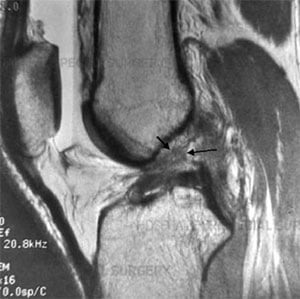

Side-view MRI showing a completely torn ACL.